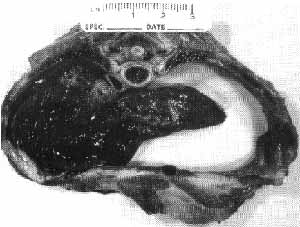

As the ribs bow out, the heart and other organs may be pushed into the pleural cavity and displace or decrease the air volume of the lungs; as a result, untreated pups become lethargic, lacking in energy and strength. By the third to fourth week, when normal pups would be running around, affected pups have not yet learned to push themselves up into a standing position. If the extended limbs, especially front legs, are moved at all, it is with a paddling motion to the sides, hence the disorder is called “Swimming-Puppy Syndrome.” The hind legs typically are extremely weak; they may be tucked under the torso, or less frequently extend behind the pup, but in either case they have little or no movement. “Swimmers” have very poor circulation, respiration, and ability to swallow food or keep milk in their stomachs, and as they are old enough to wean, are very slow when eating from pans. Stifles may be rotated underneath the belly, patellas are often luxated, and other orthopedic or osteochondral defects may be noted. Many die from inhalation pneumonia (from inspiring regurgitated milk) or other forms of respiratory failure.

She had two swimmers, each 12 oz at birth, never left on flat surface; she said she put them on blankets, “facing upwards and they stayed in a upright position,” and claimed they were both fine within weeks. The syndrome of swimmer puppies is sometimes referred to as Pectus Excavatum, and described by her as “a condition of ‘so called’ flat chested puppies.” Without intervention, and often despite efforts, they usually die anywhere from two days to four weeks of age. Sooner more often than later, according to the Bulldog people I heard from. When nursing (if it is able to get to the treat at all), the puppy may arch its back extremely in a backward movement to compensate for an apparent inability to flex at the neck.